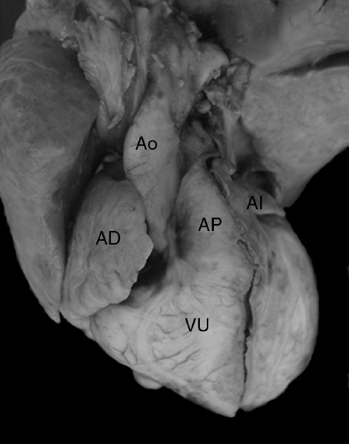

Los 2 corazones formaron parte de un situs solitus auricular, ambos con doble entrada a ventrículo único a través de una válvula auriculoventricular común cuyas valvas estuvieron adosadas a la pared ventricular; las grandes arterias normalmente relacionadas emergieron del ventrículo único con estenosis pulmonar infundibular y valvular (Fig. 5); el adosamiento y desplazamiento valvares cubrieron toda la porción de entrada y la zona trabecular posterior hasta la región apical con una gran auricularización del ventrículo único; estuvieron ausentes las cuerdas tendinosas y los músculos papilares (Fig. 6); la porción funcional efectiva del ventrículo se redujo a la zona trabecular anterior y a la región infundibular (Fig. 5). En el segundo corazón las grandes arterias estuvieron también normalmente relacionadas pero con dilatación y ambas emergieron del ventrículo único (Fig. 7). El adosamiento y desplazamiento valvares estuvieron reducidos a la porción proximal de la válvula por lo que la auricularización fue menor y mayor la porción funcional del ventrículo único (Fig. 8). Ambos corazones tuvieron un tabique interauricular pequeño con foramen primum (Tabla 1).

Figura 7 Vista externa frontal de un corazón en situs solitus auricular con ventrículo único que muestra la emergencia de las grandes arterias normalmente relacionadas a partir de esta cámara. AD: aurícula derecha; AI: aurícula izquierda; FP: foramen primum; VU: ventrículo único.